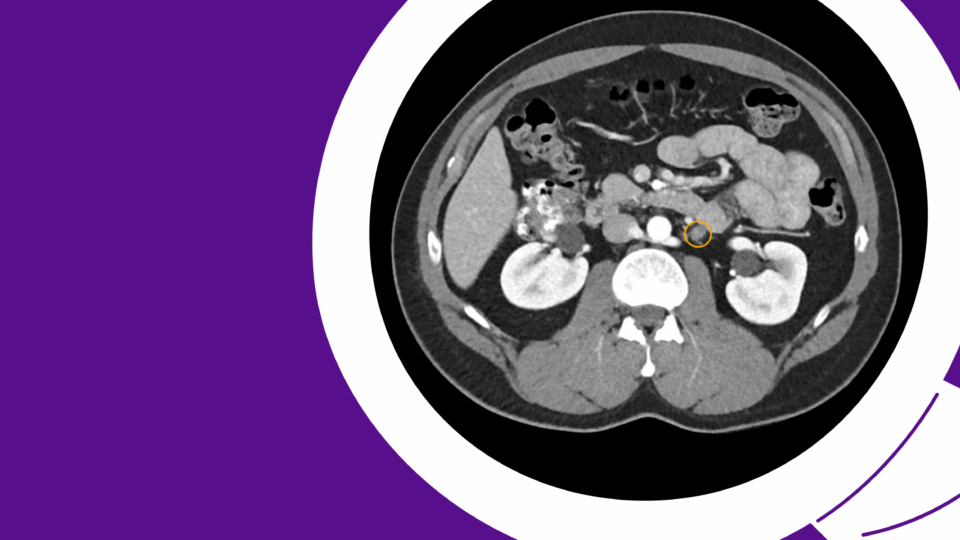

New SP Technique Advances Right-Sided Donor Nephrectomy

Surgeons develop a single-port, retroperitoneal approach for kidney donation that supports rapid recovery without compromising outcomes.